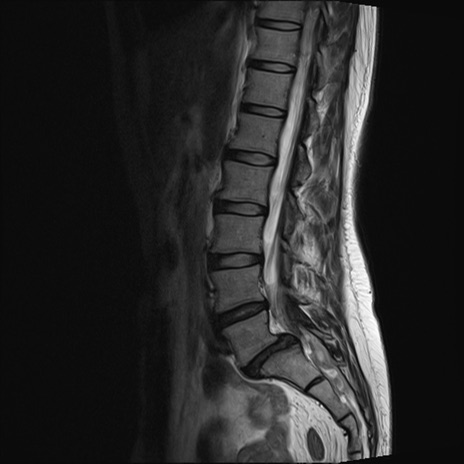

【整形】TIPS症例4 腰椎MRI T2WI(矢状断像)

腰椎MRI

T1WI(矢状断像)